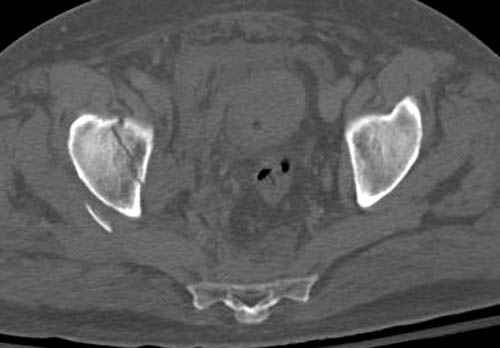

По возможности вышлите снимки, сканы таза до

реконструкции, интраоперационные.

По снимку создается впечатление о высоком поперечном переломе, задней колонны, стенки; почему не пользовались *magic screw*?

Латеральное положение облегчает проведение тракции через вертел, за 5 мм стержень за вертел (грузом через тракционное приспособление), на обычном рентгенопрозрачном операционном столе, а для положения на животе, наверное, Judet Table более приемлем, потому что там имеется латеральное тракционное устроиство.

Снимки здесь....